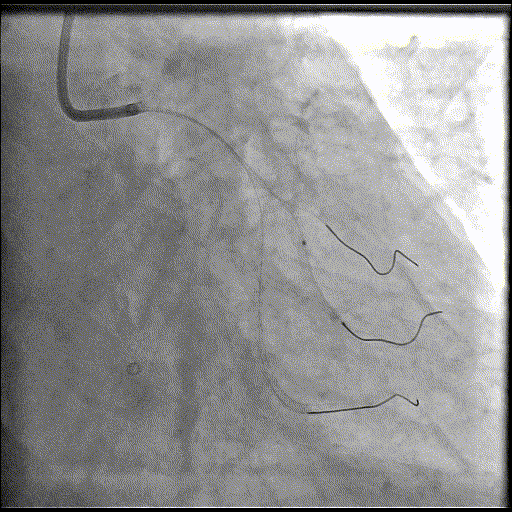

LAD处理:

球囊预扩

用预扩球囊扩张LAD病变,支架无法通过。为了解血管病变分布情况及钙化程度,遂启用IVUS检查。

术前腔内影像学IVUS指导

IVUS提示LAD近中段钙化病变,中段可见360°环形钙化。

冲击波球囊治疗

3.0x12@4atm 冠脉血管内冲击波导管顺利推送至前降支近端,但无法通过成角钙化处,故于血管近端就地进行10个周期治疗,复查造影见近端狭窄明显减轻;再次选择2.5x12@4atm冠脉血管内冲击波导管推送至成角钙化处,逐步掘进扩张病变并给予冲击波治疗,最终顺利通过成角钙化处,并于前降支中段再次进行10个周期的冲击波治疗。

支架植入并后扩

于LAD近中段串联植入两枚药物洗脱支架,经非顺应性球囊后扩张支架,复查造影及IVUS提示支架膨胀完全,贴壁良好,无夹层撕裂。